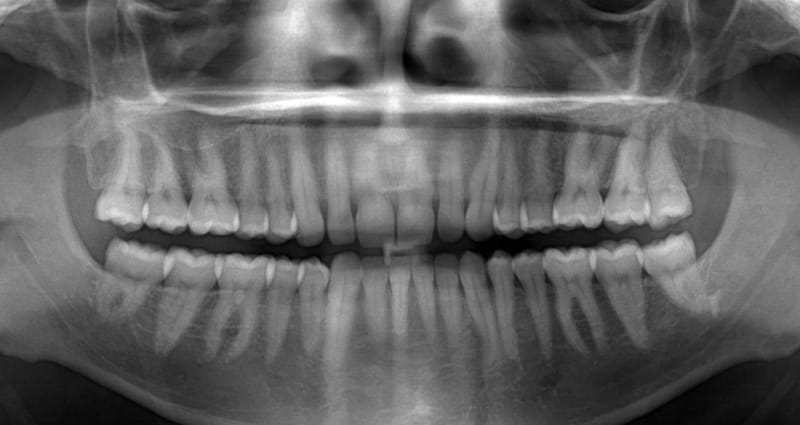

При правильной организации лечения и наличии рентген-снимков зубов с описанием (см. фото) вам вряд ли потребуется повторное посещение кабинета рентгенолога.

- Панорамная рентгенография зубов. Если стоматолог направляет вас на ортопантомограмму, и вы не знаете, как называется рентген всех зубов, имейте в виду, что речь идет именно о панорамном снимке. Не каждая стоматологическая клиника располагает необходимым оборудованием для его выполнения. Процесс заключается в поэтапной съемке всей челюсти от одного края до другого. Для обеспечения четкости изображения голову и шею обычно фиксируют.

Панорамный снимок дает возможность увидеть всю челюсть целиком.

Тем не менее, рентген зубов (см. фото) рекомендуется делать, прежде всего, при наличии инфекционного заболевания в ротовой полости, которое может негативно сказаться на здоровье ребёнка.